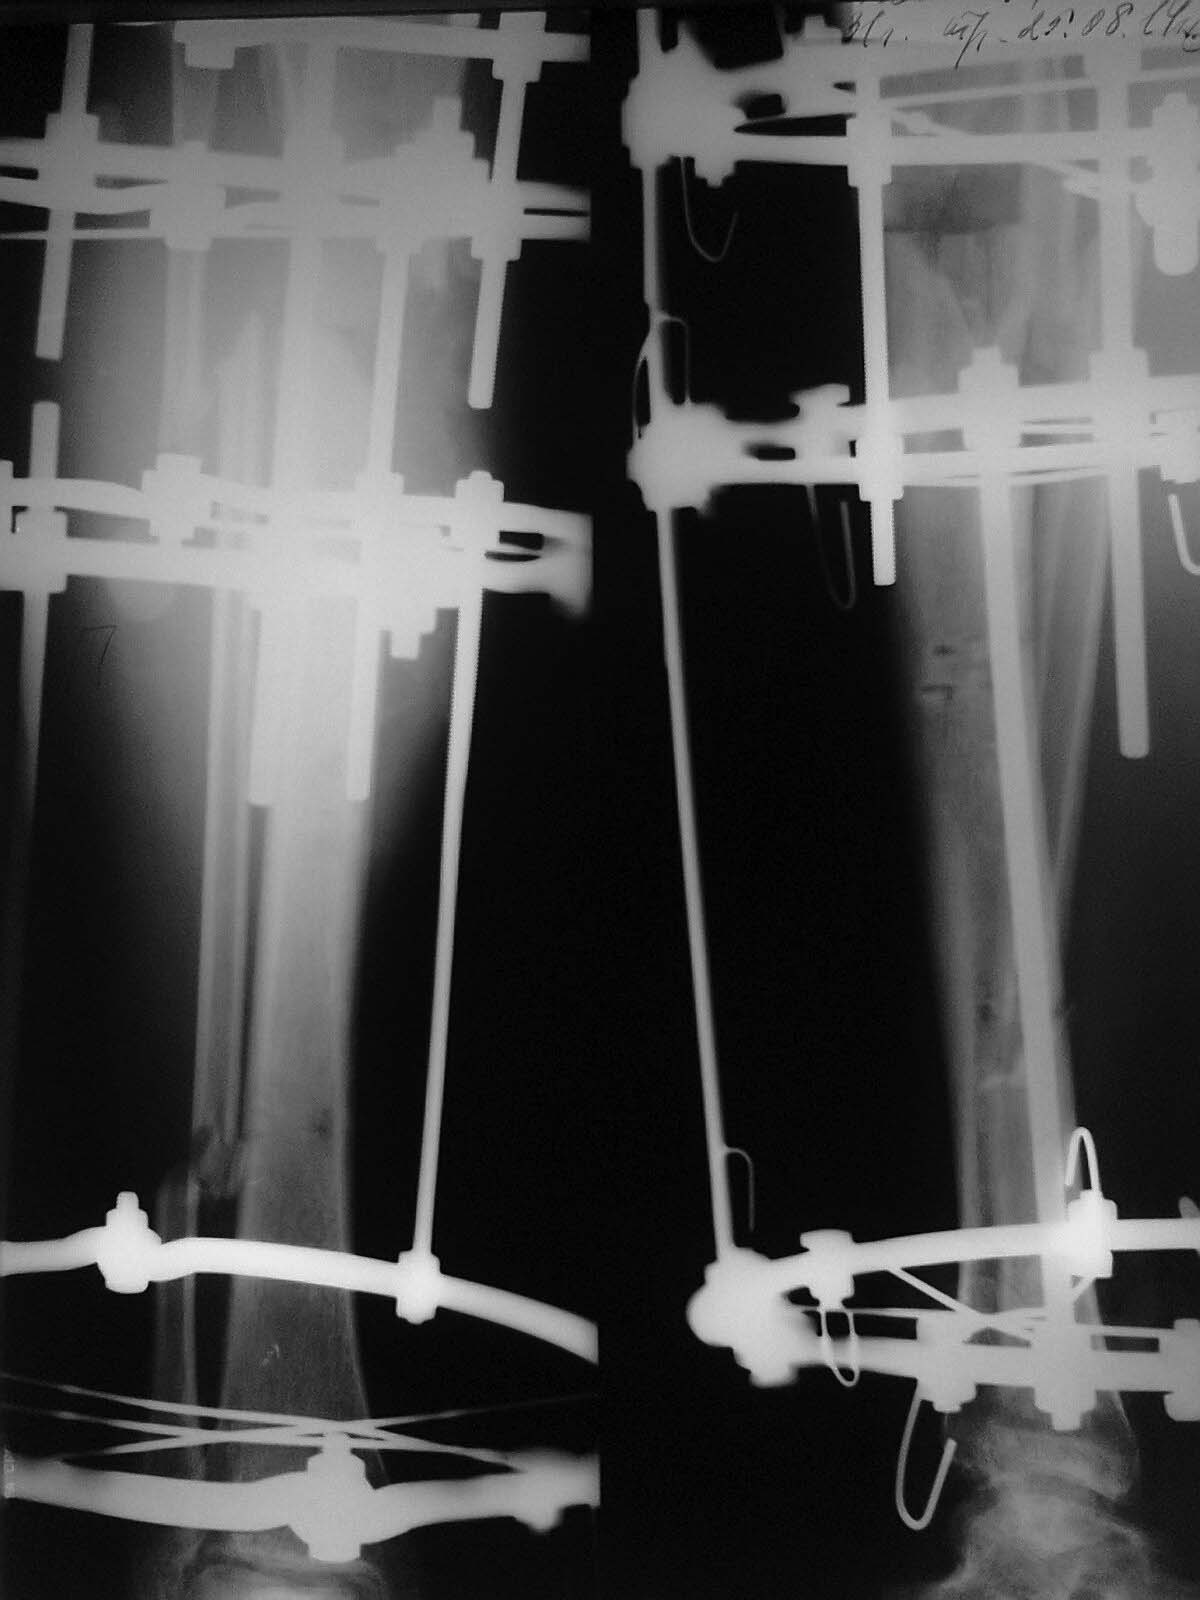

Доброго времени суток, уважаемые коллеги!Прошу Вашей помощи в лечении пациента Н. Пациент, 33 г. Травма в мае 2014 года в результате ДТП (сбит машиной). Оперирован в институте (или центре) травматологии и ортопедии одной из среднеазиатских республик (уроженец этой республики). Обратился к нам в августе, по поводу наличия гнойной раны внутренней поверхности голени с обильным отделяемым. (Рентгенограммы- фото 1). Выполнено: остенекрсеквестрэктомия, резекция концов отломков, перемонтаж аппарата (фото 2). Рана успешно зажила, пациент исчез из вида. Неделю назад пришел снимать аппарат с рентгенограммами (фото 3,4). Ходит с полной безболезненной нагрузкой на конечность, АВФ стабилен, раны от опорных элементов спокойны, отек конечности умеренный, в проекции бывшей гнойной раны- втянутый рубец (если необходим внешний вид конечности, то смогу выложить на следующей неделе,наверное). Учитывая большой дефект кости по задней поверхности кости, боимся, что при нагрузке без аппарата произойдет перелом. Вопрос: что делать? Наши варианты: 1.снять АВФ, рассверлить канал, установить штифт с антибактериальной мантией в виде "протеза" кости; 2.Резекция дефектного участка, остеотомия в н/3, перемонтаж АВФ и билокальное замещение дефекта. Что Вы посоветуете? Спасибо всем откликнувшимся.